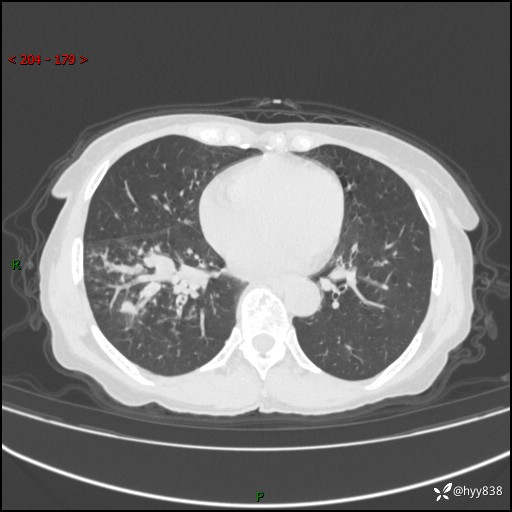

患者性别:男

患者年龄:69岁

简要病史:咳嗽咳痰2月,夜间加重

临床诊断:感染

胸部CT平扫